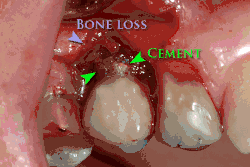

Beyond the possibility of mechanical failure[98] which may be due to poor prosthetic fitment, wear and tear, or user-induced actions such as bruxism, dental implants are also subject to peri-implant mucositis and peri-implantitis, where gum tissue and bone mass around the implant are resorbed, and the implant gradually becomes loose, and has to be removed.[99][100] In addition, although titanium is generally well tolerated by the body, there have been cases where the build-up of titanium particles released by the implant may cause systemic inflammatory response.[101] Because there is no dental enamel on an implant, it does not fail due to cavities like natural teeth. While large-scale, long-term studies are scarce, several systematic reviews estimate the long-term (five to ten years) survival of dental implants at 93–98 percent depending on their clinical use.[15][16][17] During initial development of implant retained teeth, all crowns were attached to the teeth with screws, but more recent advancements have allowed placement of crowns on the abutments with dental cement (akin to placing a crown on a tooth). This has created the potential for cement, that escapes from under the crown during cementation to get caught in the gingiva and create a peri-implantitis (see picture below). While the complication can occur, there does not appear to be any additional peri-implantitis in cement-retained crowns compared to screw-retained crowns overall.[102] In compound implants (two stage implants), between the actual implant and the superstructure (abutment) are gaps and cavities into which bacteria can penetrate from the oral cavity. Later these bacteria will return into the adjacent tissue and can cause periimplantitis.